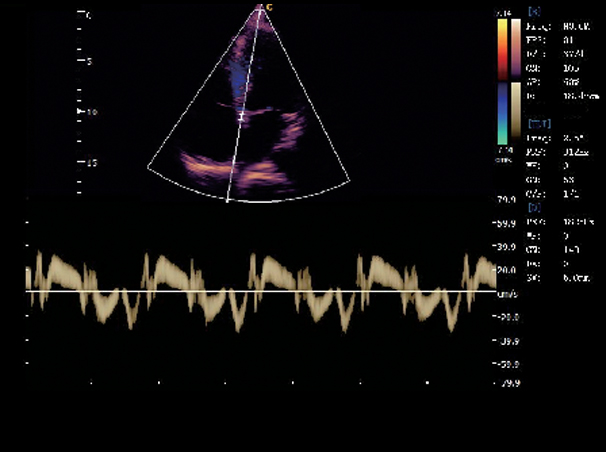

Interventricular Septum, TDI Mode